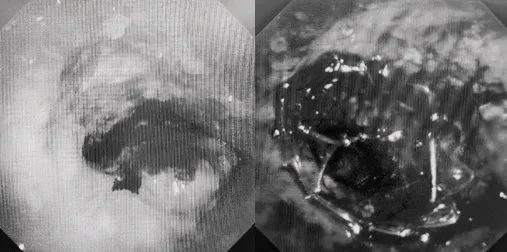

1月10日,在麻醉手术中心全力配合下,欧阳海峰带领呼吸介入团队,历时40分钟快速置入硬质支气管镜、铲切肿瘤,并顺利植入全覆膜TTS支气管金属支架。患者气短症状即刻缓解,为患者赢得了宝贵的后续治疗机会。

欧阳海峰介绍,良恶性病变导致的气道梗阻、气道异物,严重威胁患者生命安全。呼吸介入治疗是快速有效的手段,但存在巨大风险。西安国际医学中心医院胸科医院拥有专业的团队、完善的设备、全面的备用耗材和工具。呼吸内科一病区携手120急救站及医院门诊急救中心、耳鼻咽喉外科、胸外科、麻醉手术中心、影像诊疗中心、RICU等科室,已正式开通西北地区首条气道梗阻紧急救治通道,致力于为患者提供快速一站式解决方案。